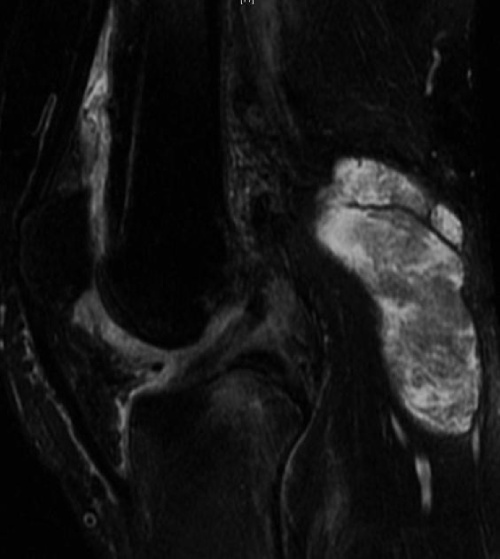

Chụp MRi ở khớp gối

Chụp MRI ở khớp gối của bệnh nhân nữ mắc bệnh viêm khớp dạng thấp phát hiện nang Baker lớn có chứa các mô mềm không đồng nhất. Ảnh: Radiopaedia